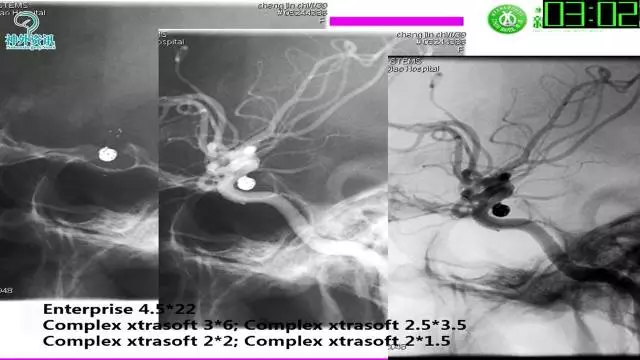

今天为大家分享的是“强生医疗CNV-神经介入专栏”第三十六期,由重庆第三军医大学附属新桥医院神经外科刘俊带来的“Galaxy弹簧圈在不规则动脉瘤中的临床应用”精彩讲课视频及PPT,欢迎观看。文章仅代表作者个人观点,如有不同见解,欢迎同道斧正!